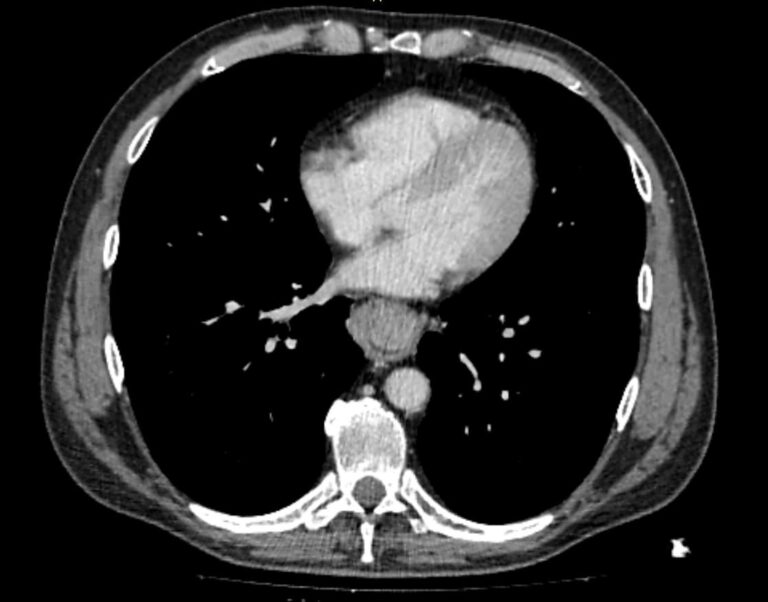

Иногда для наиболее полной и точной визуализации патологических изменений бывает недостаточно нативного исследования, особенно это касается выявления опухолевых образований пищевода малых размеров. В этих случаях проводится внутривенное болюсное контрастирование, которое предусматривает введение в вену контрастного препарата на основе йода.

Контрастный препарат с током крови попадает в патологический очаг, накапливается в нем и обеспечивает его яркую визуализацию на фоне неизмененных окружающих тканей. Данный способ диагностики позволяет выявлять опухоли на ранней стадии, что является определяющим фактором для своевременного установления диагноза и назначения эффективного лечения. Контрастное вещество полностью выводится из организма преимущественно почками в течение последующих суток.